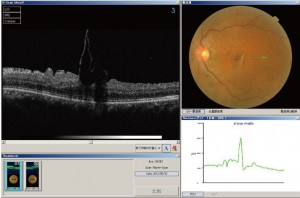

下図が網膜前膜の光干渉断層計(OCT)写真です.

網膜前膜